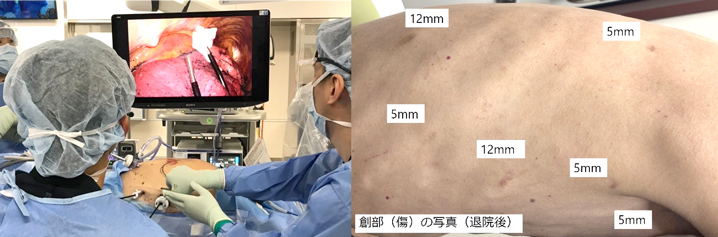

きずが小さい手術(低侵襲手術:胸腔鏡・腹腔鏡手術[ロボット支援下手術を含む])を積極的に実施しています。進行がんに対しても安全性が確保できると判断した症例では実施しています。きずが小さいと美容面で有利なだけでなく、早期の回復が期待できます。

当チームでは「術後の痛みを十分に取り除くことは患者さまの権利」と考えています。そのため、手術のきずを小さくするだけでなく、手術直後から複数の鎮痛法を併用することで、患者さまから好評を得ています。また術後の痛みを積極的に取り除くことで、早期のリハビリが可能となり、早期回復につながっていると考えています。